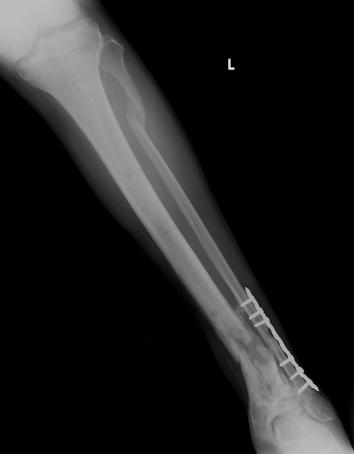

Post-corrective surgery X-Rays of the damaged right & left legs / ankles

The first two x-rays show Liam’s left ankle and pelvis prior to the accident. For comparison purposes it is interesting to see the

differences. The next x-rays were taken after the corrective surgery performed by Dr. Armendariz. Noticed that Dr. Armendariz has used tibia

bracing and also aligned the bone fragments of the left leg so that they could heal in the proper orientation. The external fixation has been

removed and Liam’s left foot has been returned to a more natural alignment.